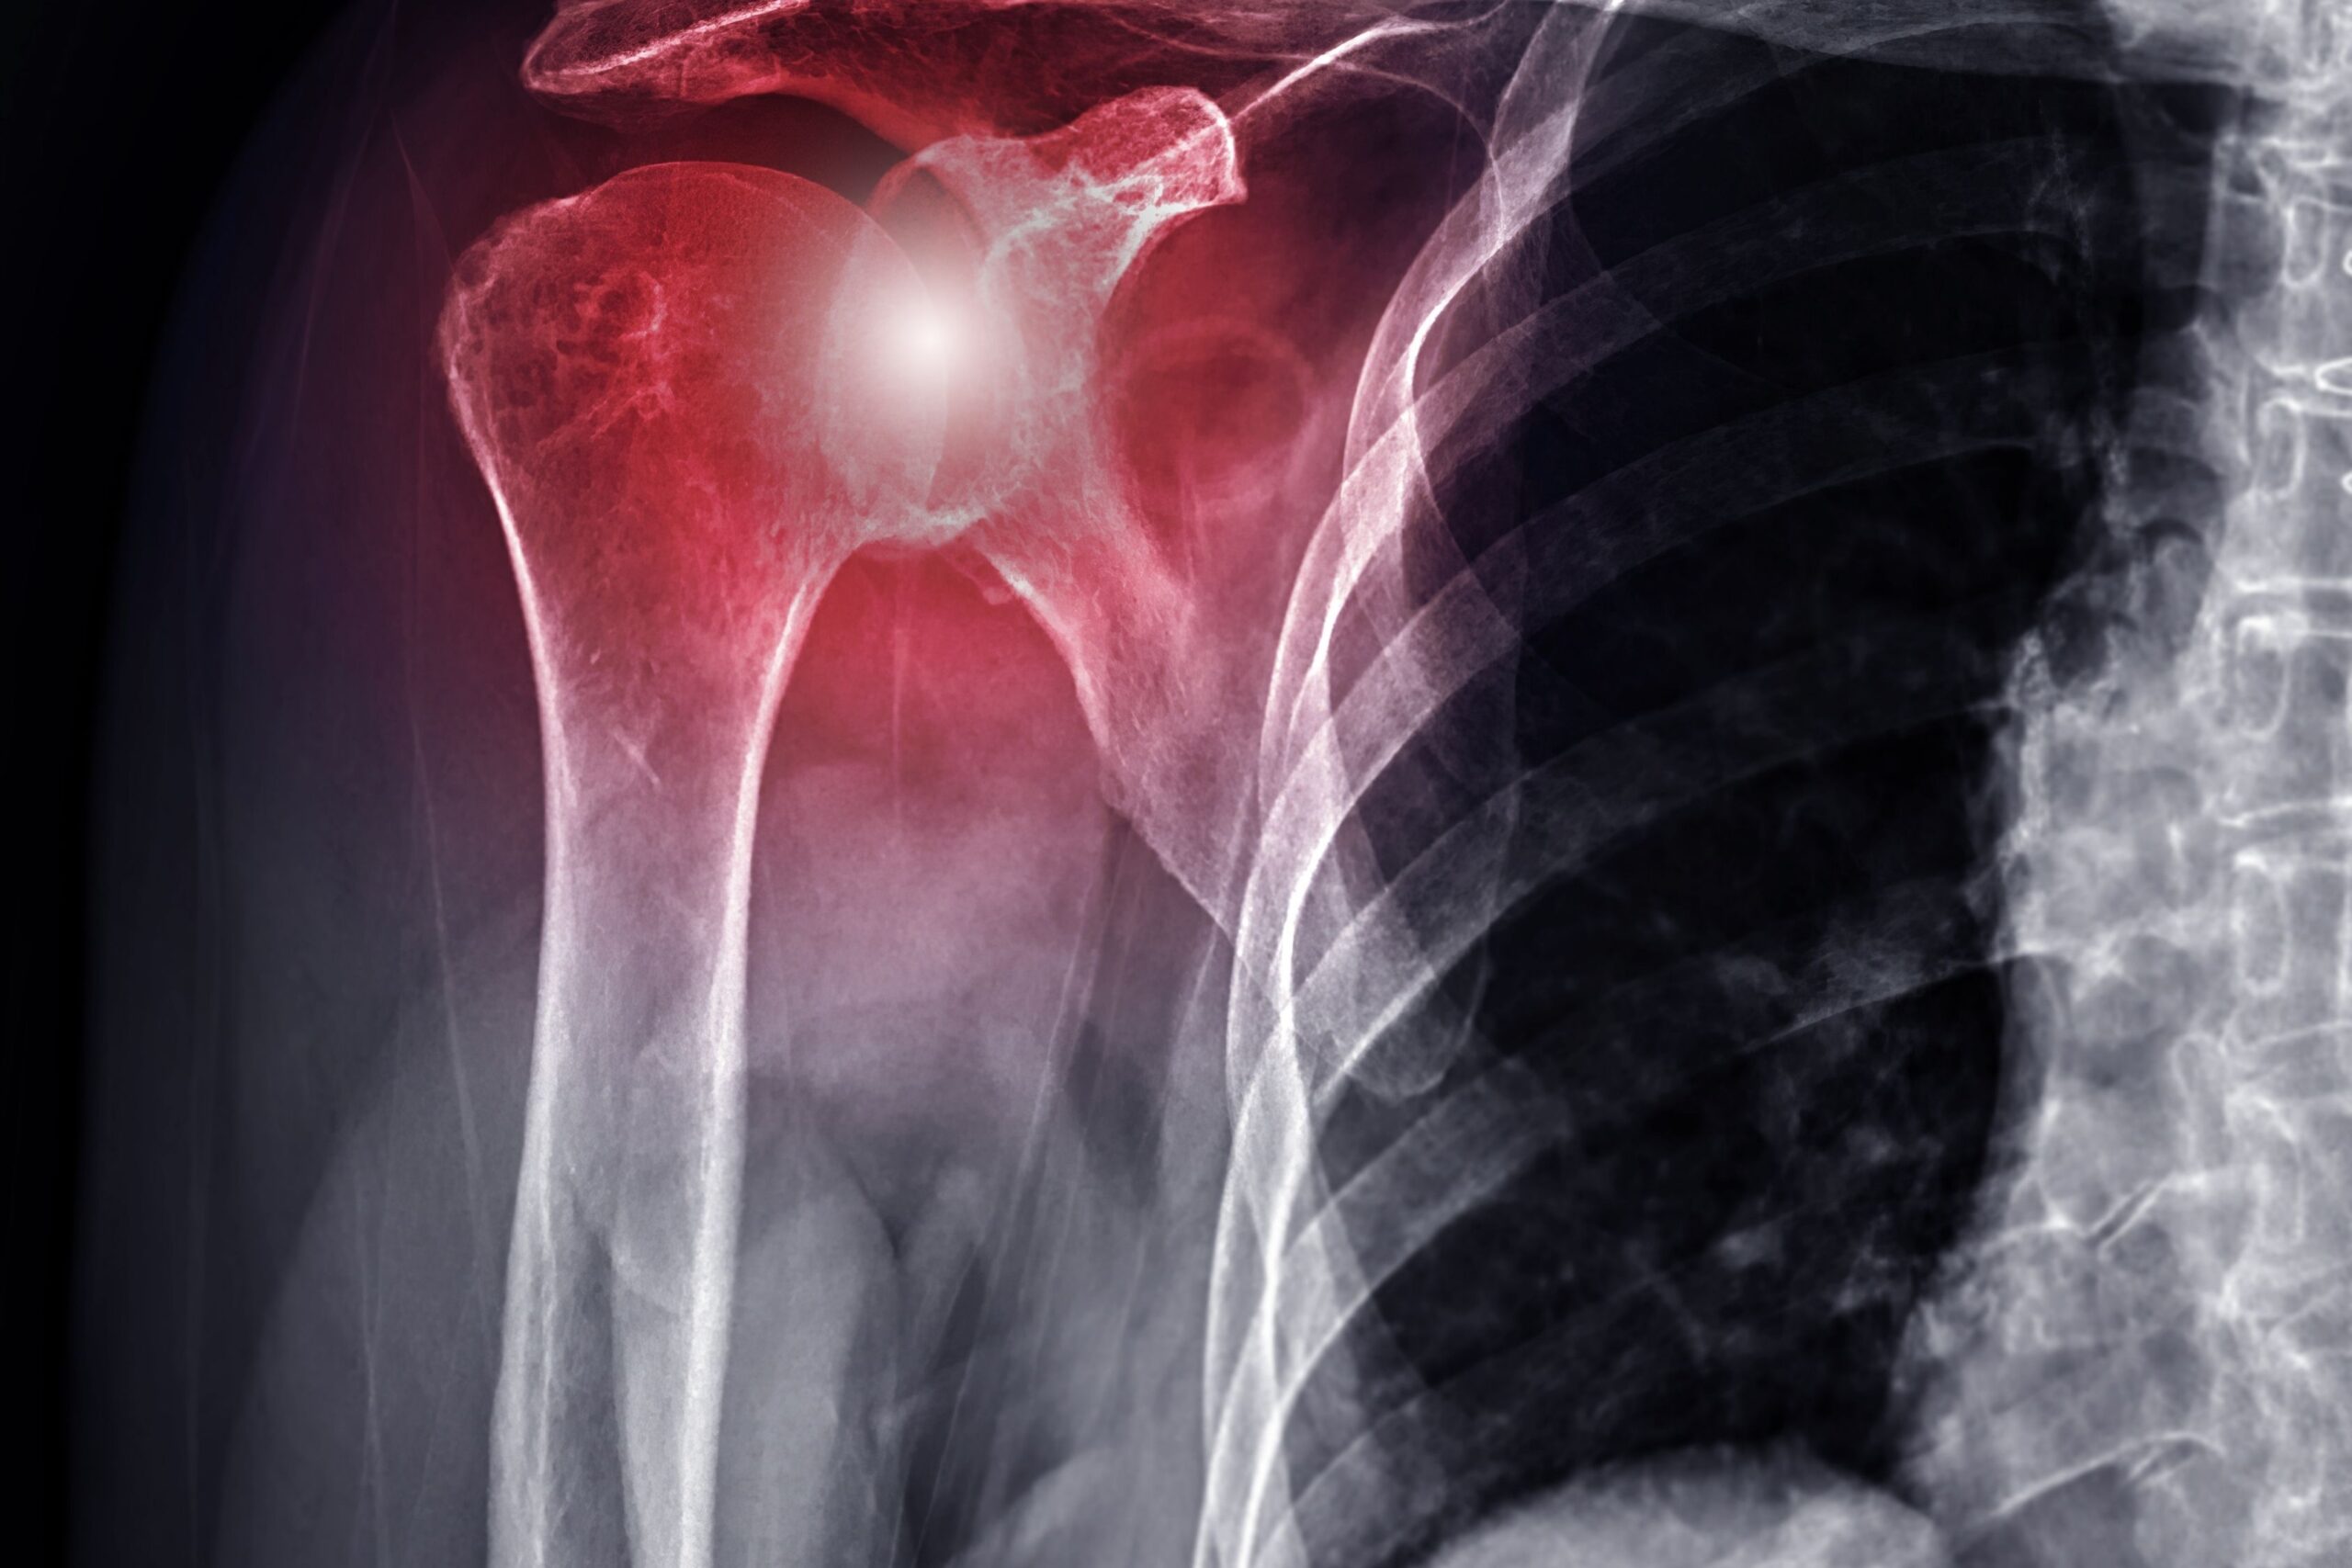

Esistono evidenze, per esempio, che la presenza di diabete possa anche favorire l’insorgere della capsulite adesiva della spalla, una patologia insidiosa che può richiedere fino a 3 anni per una completa guarigione.

L’idea di un team di ricerca indiano è, quindi, di sviluppare uno strumento di screening capace di individuare, tra i pazienti diabetici, quelli con un incipit di capsulite adesiva, così da iniziare i trattamenti in modo precoce. Lo studio, multicentrico, è pubblicato su Indian Journal of Endocrinology and Metabolism.